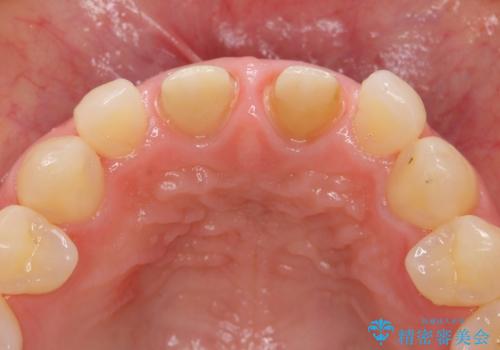

- 32万円(仮歯・ファイバーコア・ジルコニアクラウンスペシャル×2)費用は治療当時の料金となります

ただ見えるクラウンを白くきれいにするのではなく、長期的な歯の予後を考えると根管治療・ファイバーコア築盛・精密な歯牙形成等クリアすべき条件は多々あると言えます。